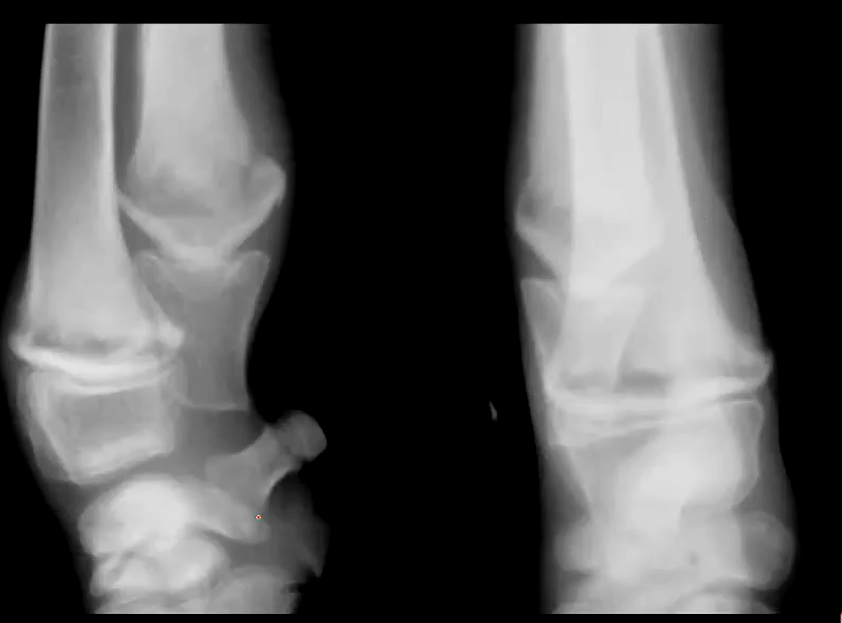

Describe panosteitis

Self limiting disease in large breed dogs that are 5-18 months old

What are the C/S of panosteitis?

Shifting leg lameness

What bones are affected with panosteitis?

Long bones

What are the early radiographic changes for panosteitis?

Increased medullary opacity

What are the middle radiographic changes of panosteitis?

Endosteal roughening, more defined opacities, mild periosteal reaction

What are the late/healed radiographic changes of panosteitis?

Hallow or lucent medullary canal, horizontal opaque bands